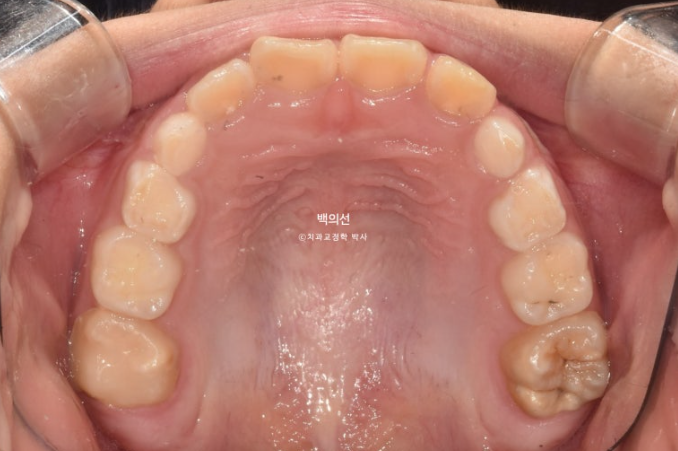

23.12

이날 공간은 별로 부족하지 않습니다.

인비절라인퍼스트 치료를 권유드렸고 아래턱의 위치를 중앙으로 재위치시키는 Mandible Advance(MA) 기능을 통해 비대칭 개선을 목표로 치료계획을 세웠습니다.

이친구의 치료계획입니다.

초반 몇 달간 영구치 맹출공간 분배와 앞니 배열 개선을 먼저 진행한 뒤 치료 중반부부터는 아래턱의 위치를 잡아주는 MA 기능이 시작됩니다.